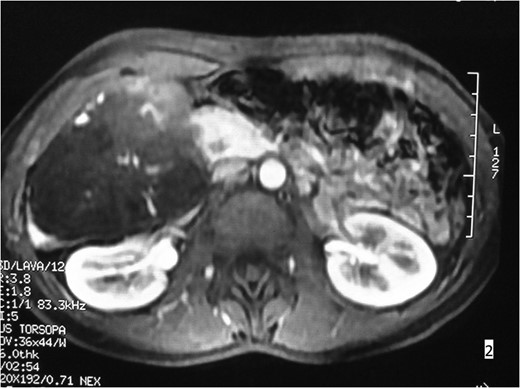

A 38-year-old woman was referred to the surgical out-patient Department of our Center presenting abdominal discomfort and recurrent episodes of acute abdominal pain during the previous 6 months. Her clinical and surgical history were free, and the patient did not mention any other symptoms. Physical examination only revealed tenderness during palpation of the right upper abdominal quadrant. Laboratory blood examination showed results within normal limits. CT-scan and MRI were ordered, in order to further investigate this condition. These imaging controls revealed the presence of a giant hemangioma (~9.6 cm in diameter), involving segments VI and VII of the liver (Figs 1 and 2). Therefore, in this symptomatic patient, considering the location, size and possible future complications of the lesion, a right segmental hepatectomy was decided.

MRI imaging. In the right hepatic lobe a lesion of 9.6 × 8.9 × 7.9 cm3 is observed, hyperdense in T2W presenting contrast enhancement.